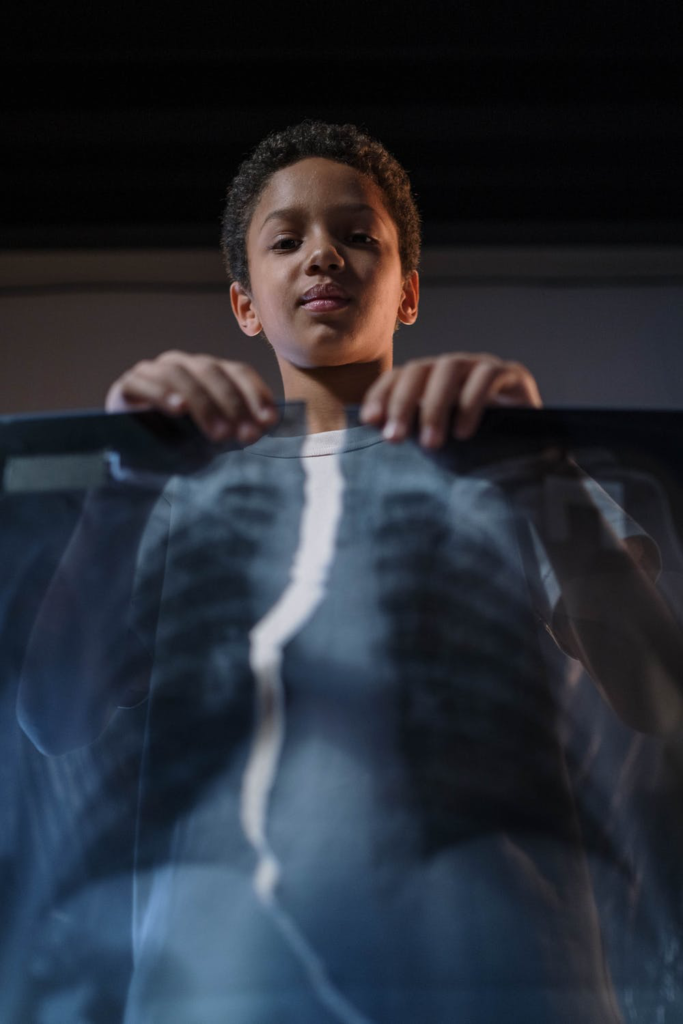

- Martínez, D (2022). Evaluación neuropsicológica de pediátrico con Púrpura de Henoch-Schönlein [Fotografía], expediente clínico, Santiago de Querétaro, México.